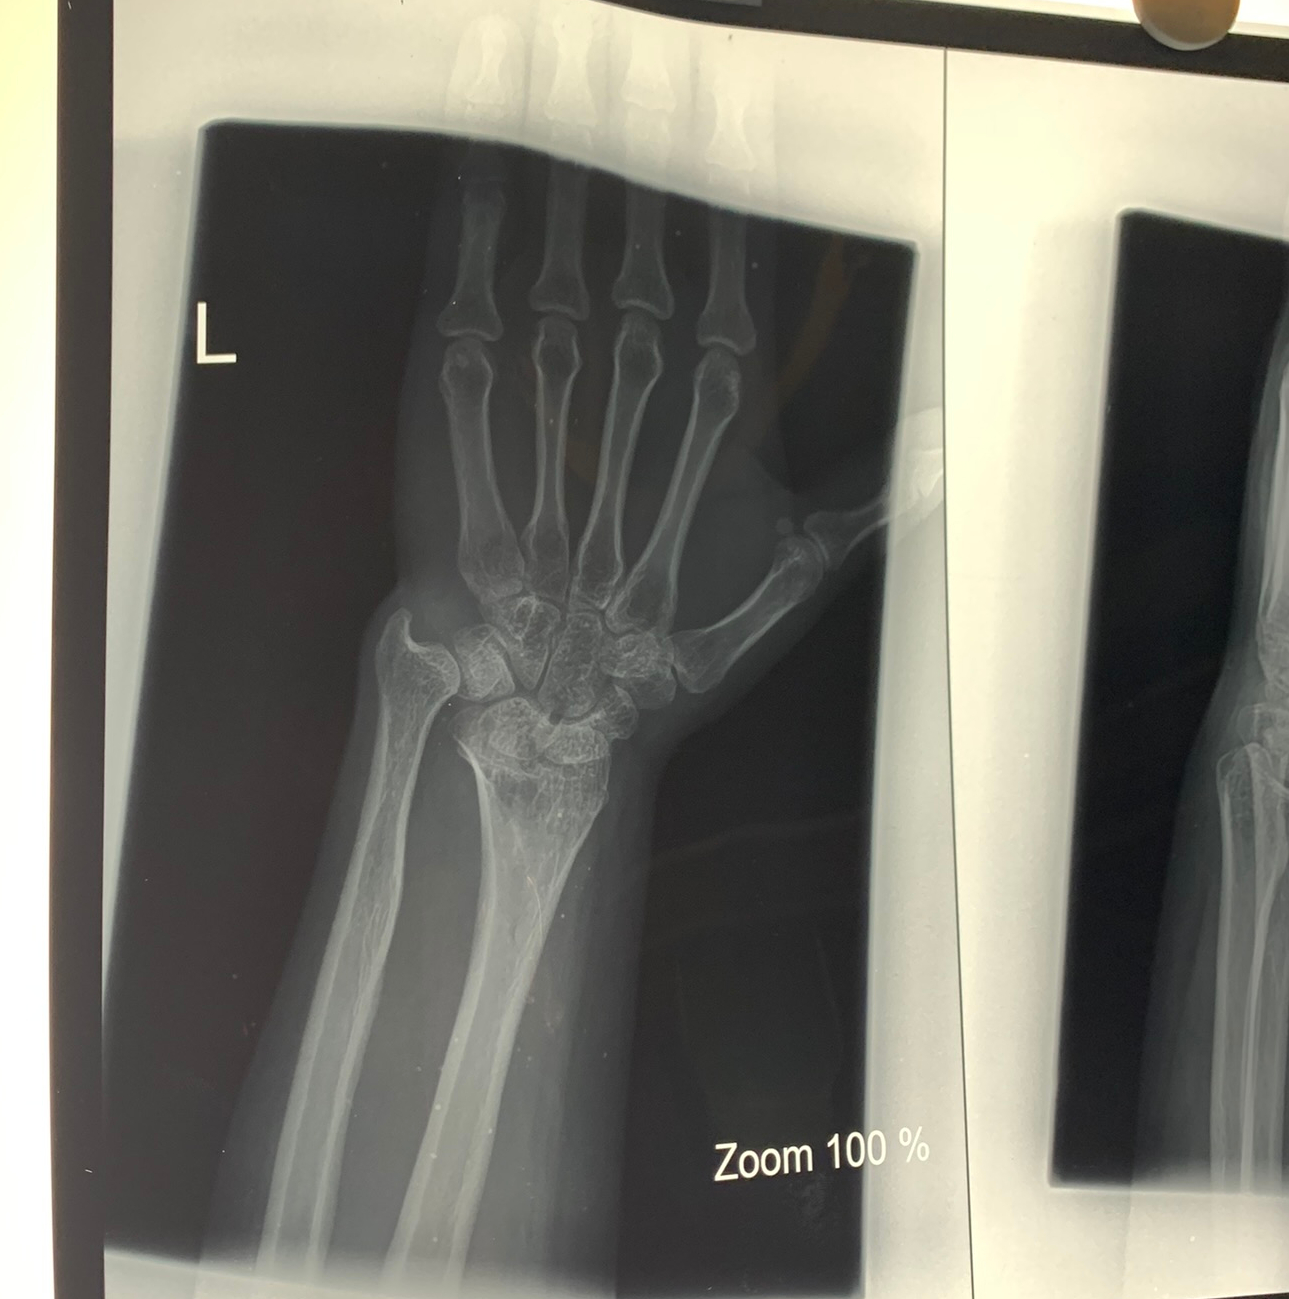

One particularly fascinating procedure involved a patient with Magelund’s deformity. This surgery required ulnar shortening, radial growth plate reshaping, shortening and fixation using plates and pins. The transformation from pre-op to post-op was profound, and witnessing the team’s precision was truly captivating.